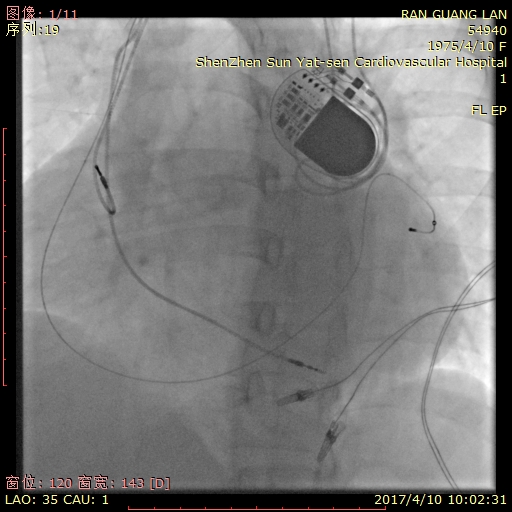

该患者升级CRT后的胸片

2017年4月10日上午,在我院导管室局部麻醉下,彭长农主任带领的起搏器与电生理团队为冉女士升级双腔起搏器为CRT-P。在植入左室电极时,由于患者血管畸形,彭主任在反复进行器械优化选择后成功植入左室电极,后续术程顺利,参数满意;术后患者血压明显较术前改善。出院时患者呼吸平顺、可平躺休息,胃口、精神明显好转,患者及家属均对手术效果非常满意,冉女士说,这下终于可以好好睡个觉了!